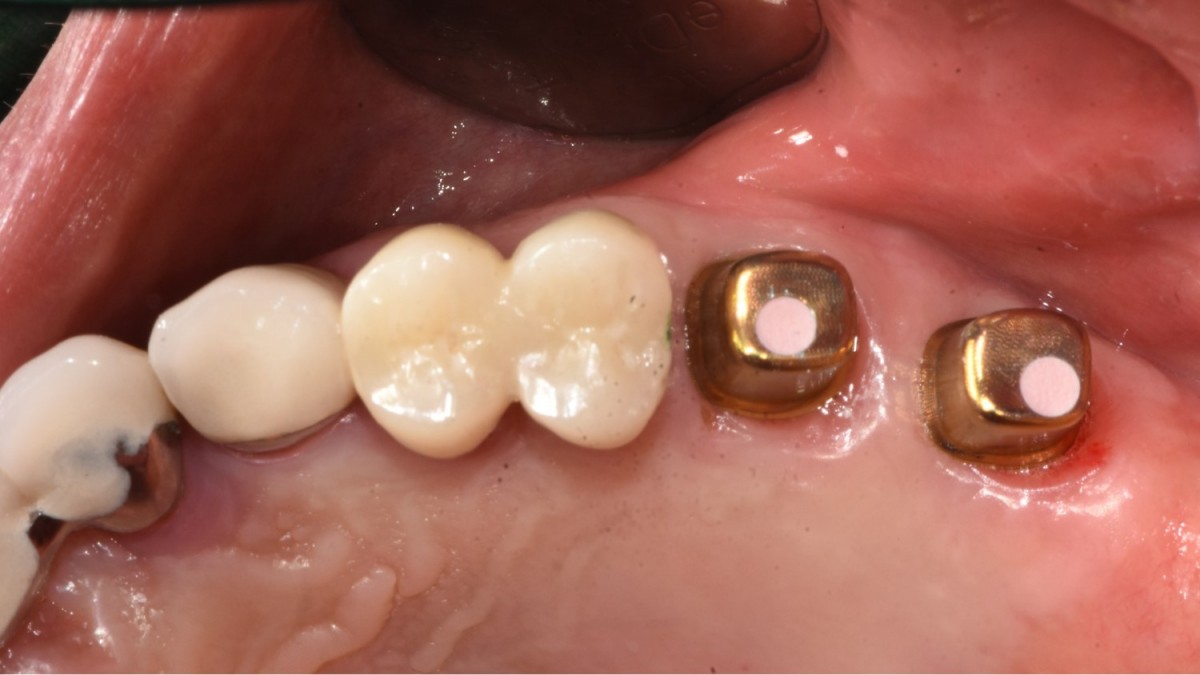

A 57-year-old male patient recently underwent

implant restoration on the maxillary right molar. This time, he is scheduled to

proceed with the left molars. (ARUM implant system)

▲2 implants were placed. ArumDentistry NB1 5*10 (30Ncm) in the 1st molar and 5*10 (10Ncm) in the 2nd molar.